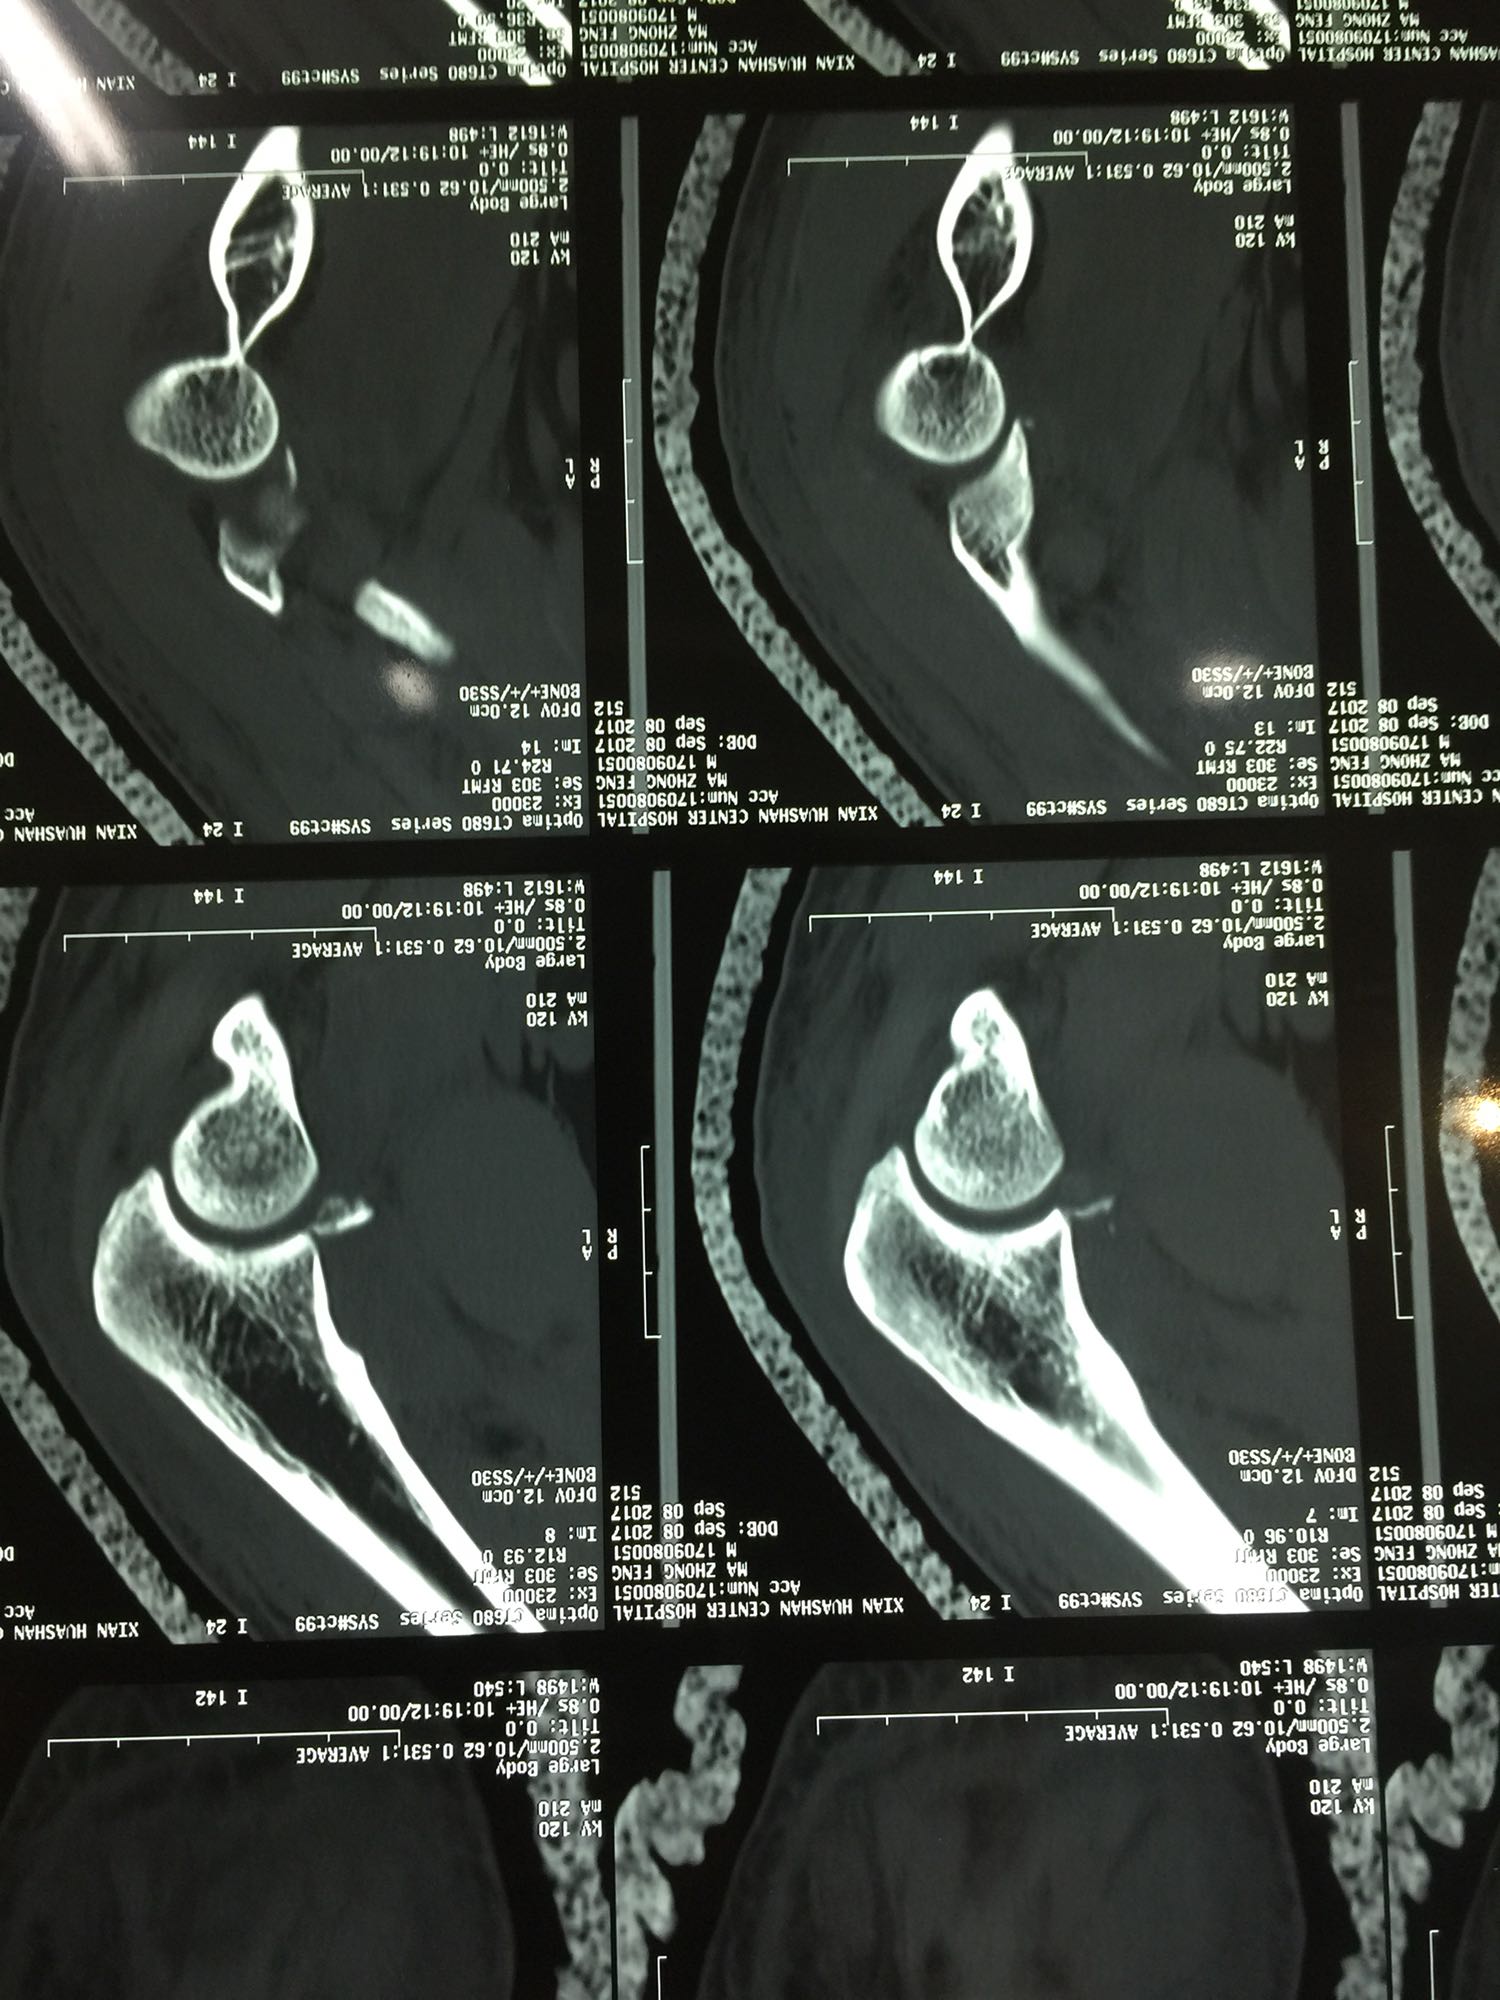

左肘关节高度肿胀,压痛强阳性,肘关节明显活动受限,末梢血运良好,各指关节运动正常。 X线片及CT如图:

1、左尺骨冠状突骨折;2、左肱骨外髁撕脱骨折 治疗:入院后伤肢石膏外固定,给予局部冷敷消肿治疗,于伤后一周行骨折手术治疗,先行前内侧切口复位固定冠状突骨折,活动肘关节发现关节明显不稳定,随取外侧切口,复位固定肱骨外髁,修补外侧副韧带,肘关节明显稳定。术中术后片子如下